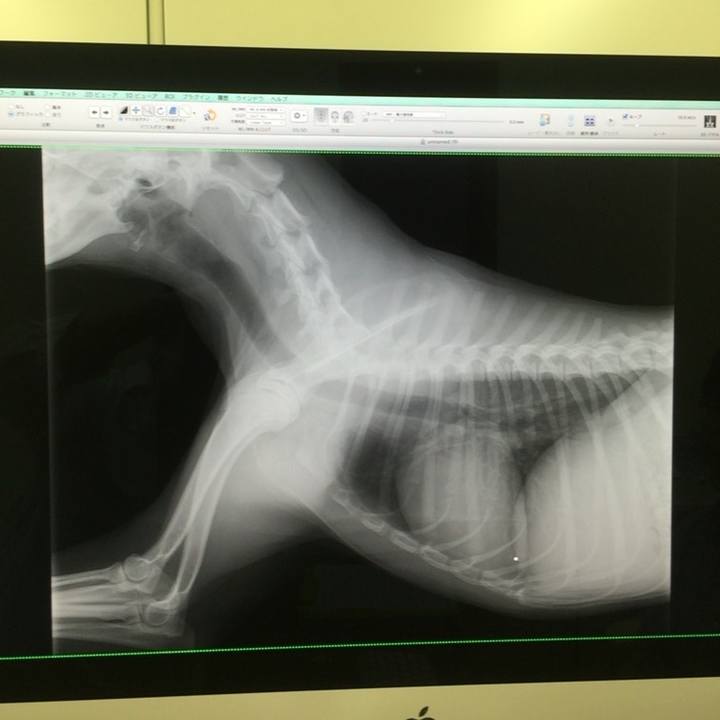

レントゲン撮らせてもろてきた。ほぼ異常なし!このまま暮らしていって問題なさそう。